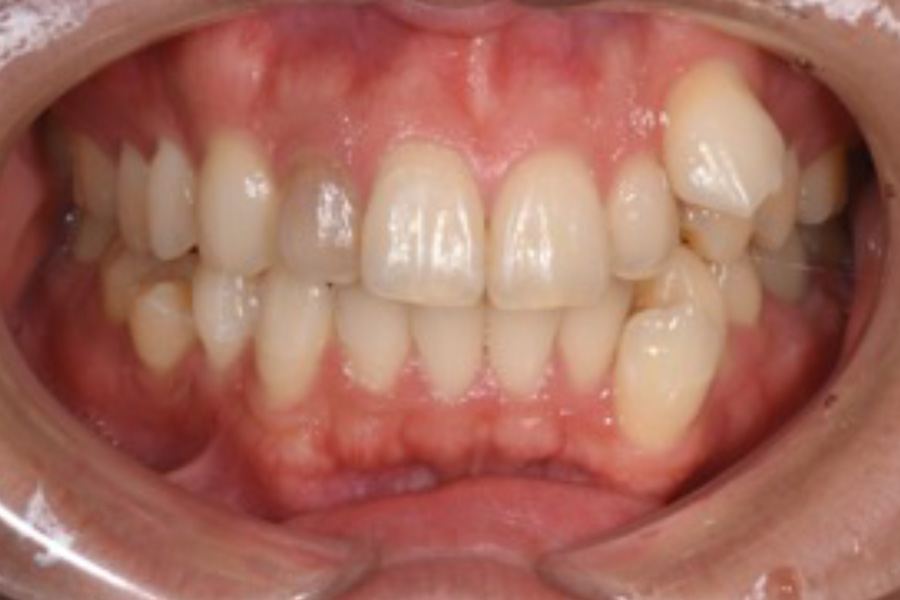

前歯がガタついている

【マウスピース矯正】

- かみ合わせが悪い。前歯がガタついている。

- 1年

- マウスピース矯正

665,500円(税込)(2025年現在)

- 目立ちにくいマウスピース矯正(非抜歯矯正)

歯と歯の間に隙間をつくることにより、歯列弓を広げながら治療を行いました。

- ・後戻りする可能性があるのでリテーナーを最低でも矯正期間以上はつけること

・稀にほっぺた、唇、舌などに口内炎や傷ができることがあります